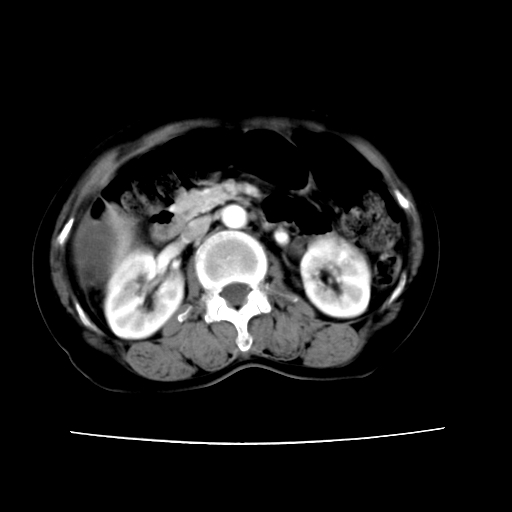

2008-6-10ct平扫

ct增强

6月份ct片显示肝内巨大混杂密度团块,伴包膜下积液(内含液液平面),增强多无明显强化。只能考虑肝占位病变,并肝内、血膜下血肿。肝ca并出血多见,而肝血管瘤并破裂出血少见。

6月份ct片显示肝内巨大混杂密度团块,伴包膜下积液(内含液液平面),增强多无明显强化。只能考虑肝占位病变,并肝内、包膜下血肿。肝ca并出血多见,而肝血管瘤并破裂出血少见。